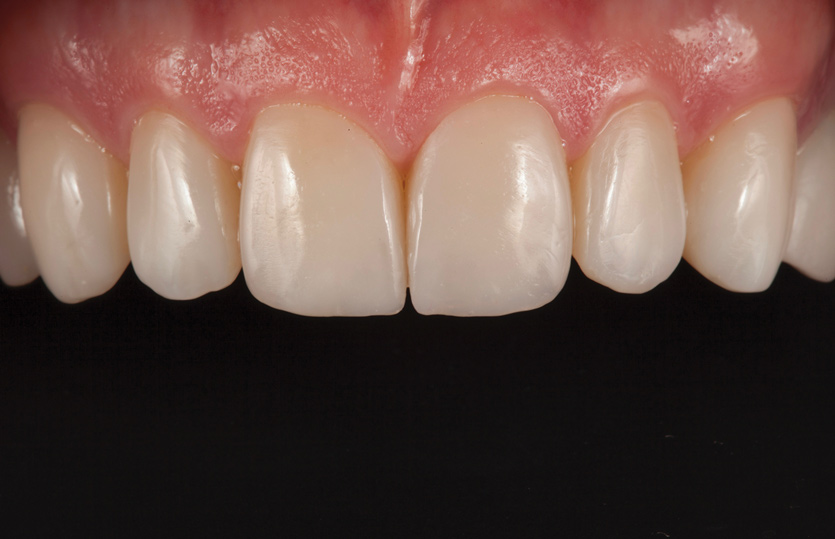

Fig 1. Preoperative smile photograph.

Figure 1

Fig 10. Postoperative smile photograph.

Figure 10